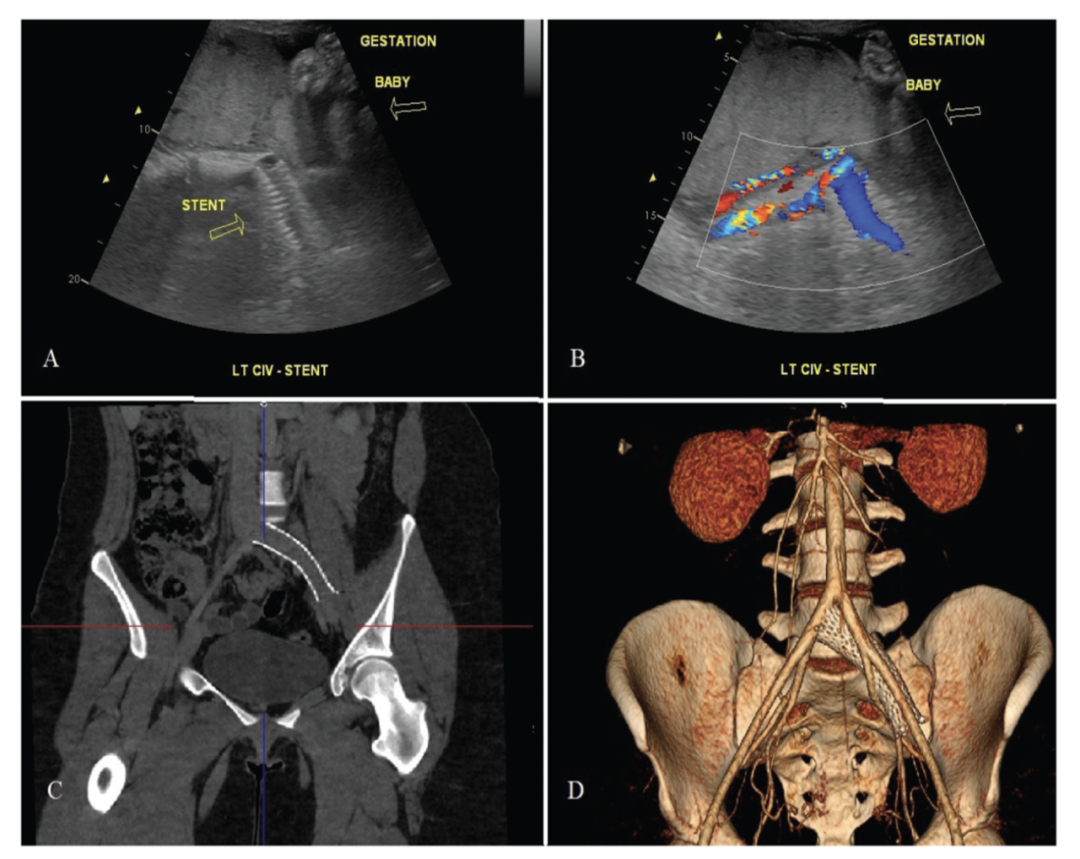

根据最近的一份新闻稿,髂静脉支架可以很好地耐受妊娠子宫,未来可能怀孕不应成为治疗盆腔静脉功能不全 (PVI) 的禁忌。

主要作者 Peter Pappas(米国新泽西州血管医学中心)指出:治疗继发于 PVI 的慢性盆腔/腿部疼痛的护理标准是髂静脉支架置入术,伴或不伴卵巢静脉栓塞。由于许多接受这种治疗的女性处于育龄期,我们评估了接受髂静脉支架植入后怀孕的女性的支架通畅率和再干预率。

在此期间,外科医生为 1,698 名女性植入了 2,046 个支架。从这个队列中,研究了 15 名接受 16 个髂静脉支架治疗 PVI 的女性的信息,这些女性有 17 次怀孕。

所有患者都接受了产后超声检查,未发现任何与妊娠相关的支架相关问题。只有一名患者失访,在其余 16 次妊娠中,在妊娠后 43 +/- 24 个月的平均时间内未观察到支架闭塞。

据作者团队所知,目前只有两篇经过同行评审的出版物讨论了随后怀孕女性的髂静脉支架置入术。2009 年,Hartung 等人报道了 6 名患有髂静脉支架的孕妇,其中三个用于非血栓形成的左髂总静脉狭窄,三个用于有症状的血栓后病变。四名妇女在怀孕 8 个月时显示了支架受压的双重扫描证据。产后,没有发现压迫的证据,也没有女性因怀孕而需要再次干预。

两名患者在妊娠前 20 个月和 37 个月因支架内再狭窄接受了妊娠前再支架治疗。从妊娠晚期开始到分娩后 1 个月,所有 6 名妇女都接受了低分子肝素治疗。注意到两名女性患有高凝状态,一名患有 XII 因子缺乏症,一名患有蛋白 C 缺乏症。2017 年,Dasari 等人报告了他们在 12 名女性中的结果。在该系列中,12 名妇女中有 11 名有深静脉血栓形成病史,1 名在妊娠 14 周时因 May-Thurner 病变继发的髂股深静脉血栓形成进行溶栓。

基于这三项调查,髂静脉 Wallstents 似乎可以很好地耐受妊娠子宫。鉴于新型镍钛合金静脉支架的径向强度增加,可以假设它们的性能同样好,甚至更好。尽管 Hartung 观察到六个支架中有四个在怀孕期间表现出受压,但没有一个需要产后再次干预。此外,Dasari 等人报道的产后静脉成形术均针对无症状的流出道狭窄进行预防性检查。作者系列中的一名产后症状患者在上次怀孕 9 年后出现与妊娠无关的流入狭窄。